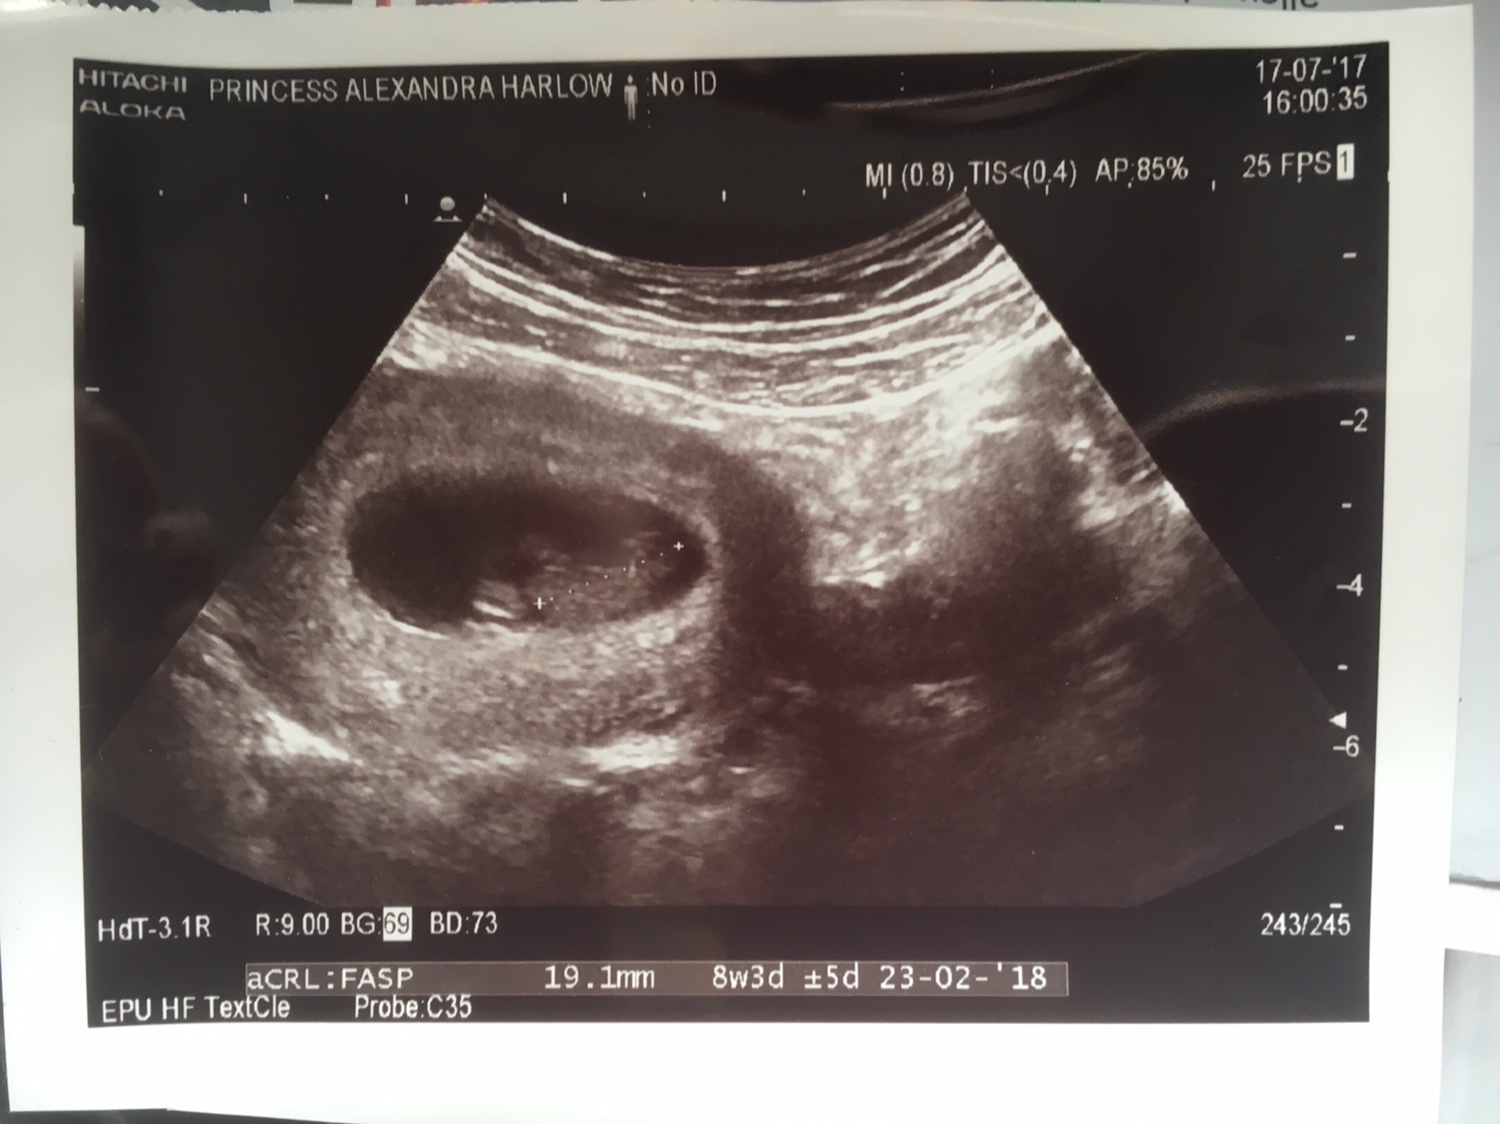

I have been reading up on the ramzi theory and wondered what you all thought of my abdominal scan taken at 8 weeks?